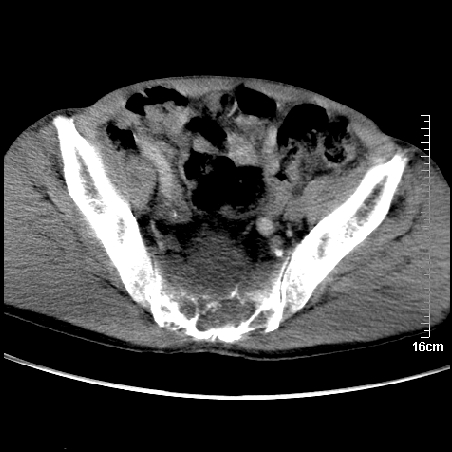

标题: CT16886:骶尾部占位:1.脊索瘤?2.巨细胞瘤? [打印本页]

标题: CT16886:骶尾部占位:1.脊索瘤?2.巨细胞瘤?

平扫:

部分骶尾骨已被软组织密度的肿瘤所取代,同意“首先考虑脊索瘤,不除外转移瘤”的意见。

1、骶尾部巨大软组织肿块,部分骶尾骨以被软组织肿块代替,呈不规则侵蚀;病变突向盆腔内;增强扫描病变呈不均质强化;首先考虑脊索瘤。不支持的一点就是病变内无钙化。